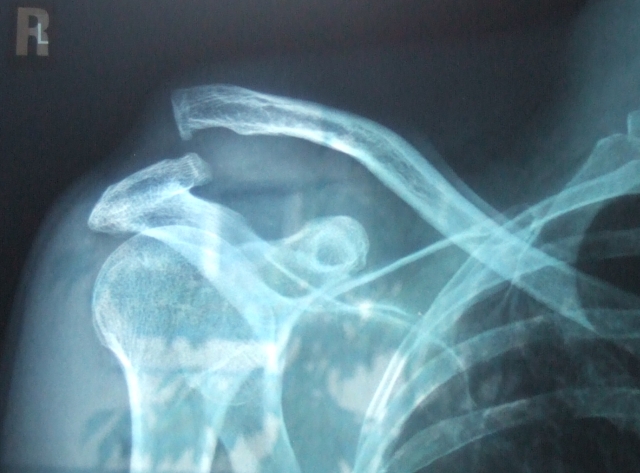

Am SIC Einsiedeln ist Daniel Langenegger schwer gestürzt und hat sich eine sogenannte Schultereckgelenksprengung zugezogen.

Das ist nebst Ausrenken der Schulter und Schlüsselbeinbruch, auch eine typische Schulterverletzung bei Inlinern und muss in einigen Fällen operiert werden.

Unten das original Röntgenbild.  Man sieht, dass das Schlüsselbein weit über der Schulterhöhe vorsteht, dies wegen den abgerissenen Bändern und dem aufgerissenen Schultereckgelenk die das Schlüsselbein nun nicht mehr mit der eigentlichen Schulterblatt  verbinden. Man sieht einen grossen Absatz oben auf der Schulter.

Irgendwie soll das in den meisten Fällen wieder zusammenwachsen und einigermassen stabil werden. Mal sehen wie es Ende August aussieht.